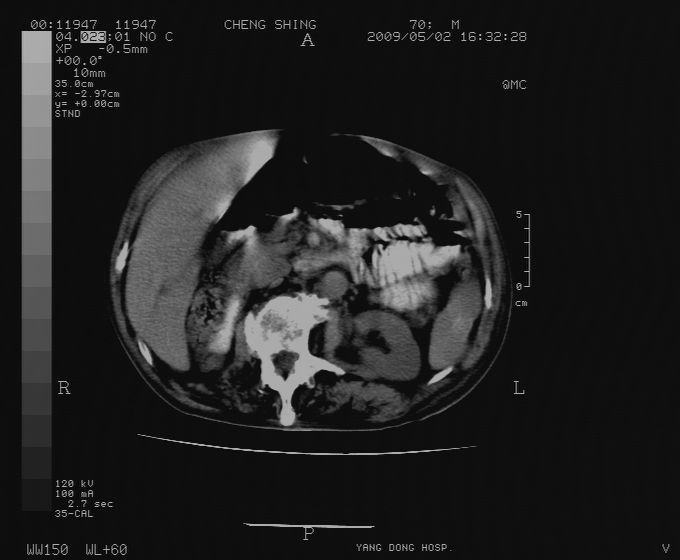

标题: CT19743:男70岁,肺部疾病入院,B超发现肝右叶占位,CT [打印本页]

标题: CT19743:男70岁,肺部疾病入院,B超发现肝右叶占位,CT

肝表面塌陷,病灶周围有子灶,前面较大子灶强化符合肝癌表现,考虑肝癌肝转移可能性大.

1)考虑肝癌并肝内转移。2)少量腹水。3)双侧胸腔积液。

1)考虑肝癌并肝内转移。2)少量腹水及双侧胸腔积液。3)椎体退变。